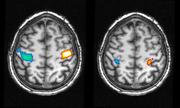

Aktivität in der motorischen Hirnrinde bei einer tatsächlich ausgeführten Bewegung der Hände im Wachen (linkes Bild) und während einer geträumten Bewegung (rechtes Bild). Blaue Regionen spiegeln die Aktivität bei einer Bewegung der rechten Hand wider, die in der linken Gehirnhälfte deutlich wird, wohingegen rote Regionen die entsprechende Bewegung der linken Hand auf der gegenüberliegenden Hirnhälfte anzeigt. MPI für Psychiatrie